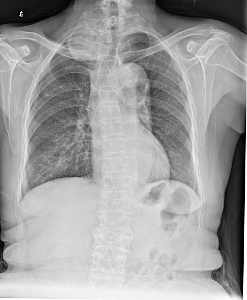

纵隔炎可分为急性化脓性感染和慢性纤维性病变二种。前者有急性感染症状,后者可引起上腔静脉压迫综合征或纵隔内其他器官受压的各种症状。 X线表现为两侧纵隔阴影增宽,以上纵隔为明显,由于炎症累及周围胸膜致使两侧轮廓较模糊。侧位胸片胸骨后密度增加。气管、主动脉弓的轮廓模糊。形成脓肿,可于纵隔的一侧或双侧见突出的弧形阴影,气管、食管受压移位。亦可出现纵隔气肿、脓肿和液平、胸腔积液、液气胸等征象。食管碘油或有机碘液造影可证实食管穿孔部位、食管支气管瘘或食管胸膜瘘。电脑断层扫描可早期发现严重的深颈部感染所致的纵隔炎。

X线检查可无异常发现,但大部分患者有纵隔胸膜增厚或上纵隔增宽,病变区可见钙化阴影。胃、十二指肠钡餐检查示食管狭窄。体层摄片示气管、支气管狭窄。血管造影有助于了解上腔静脉及其分支的梗阻情况。CT检查亦有诊断价值。[1]